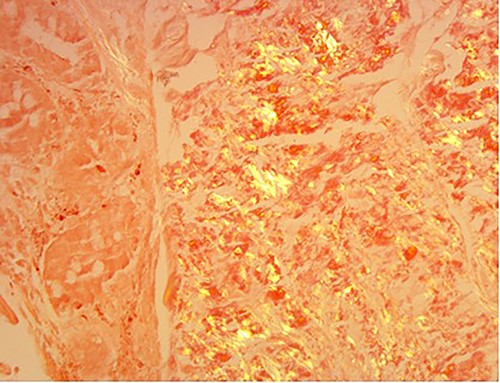

A 76-year-old lady presented to the outpatient clinic with a history of lower abdominal bloating and lethargy for 1 week. The patient denied abdominal pain, nausea, altered bowel habits or GI bleeding. Her past medical history included gastroesophageal reflux disease, ulcerative colitis and a previous hysterectomy. Physical examination exhibited pallor of the conjunctiva, distended abdomen with visible peristalsis on inspection but soft, non-tender on palpation and absence of ascites. Laboratory testing found normocytic normochromic anaemia, thrombocytosis and a positive myeloma screen with elevated kappa to lambda free light chain ratio despite normal renal and liver function. An ultrasound of the abdomen was unremarkable. Computed tomography (CT) with IV contrast of the abdomen revealed diffuse thickening of the small and large bowel with the small bowel dilated throughout. Magnetic resonance imaging of the small bowel showed multiple abnormally thickened loops of the jejunum and proximal ileum with a maximal wall thickness of 0.9 cm (Figs 1 and 2). Gastroscopy revealed severe distal oesophagitis, the stomach contained patchy telangiectasia and gastritis with sloughy mucosa at the incisura in addition to duodenitis with stricture at the second part of duodenum (D2) (Figs 3 and 4). Histopathology from the biopsies of the gastric incisura, D2 and the proximal jejunum displayed reactive changes with intramucosal haemorrhage and extensive deposition of pink amorphous, eosinophilic material on haematoxylin & eosin (H&E) stain. The deposits were predominantly seen in the proximal jejunum with a positive Congo red stain showing apple-green birefringence under polarized light (Figs 5 and 6). The patient was referred to Haematology, and a bone marrow aspirate and trephine biopsy revealed proliferation of 15% mature plasma cells consistent with the diagnosis of myeloma.

Amyloid stain on proximal jejunum biopsy as seen under polarized light showing apple-green birefringence (Congo Red ×20).

The investigation for AL amyloidosis should include testing of serum and urine for monoclonal light chains by immunoelectrophoresis and immunofixation followed by a bone marrow aspirate for quantification of the number of plasma cells as well as to establish presence of monoclonal chains. Endoscopic examinations and biopsy is beneficial; however, some patients may require push enteroscopy or capsule endoscopy to detect lesions that are limited to the jejunum [3]. The gold standard for diagnosing amyloidosis remains visualization of the characteristic green birefringence under polarized light following Congo red staining of the tissue biopsy [3].